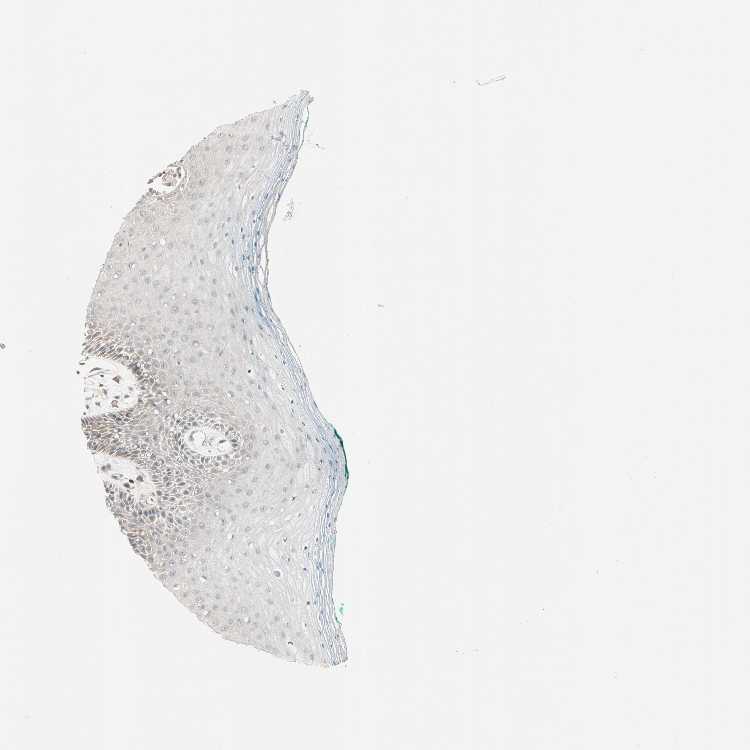

ORAL MUCOSA - Antibody stainingi

Antibody staining in the annotated cell types in the current human tissue is reported as not detected, low, medium, or high, based on conventional immunohistochemistry profiling in selected tissues. This score is based on the combination of the staining intensity and fraction of stained cells.

Each image is clickable and will lead to virtual microscopy that enables deeper exploration of all samples and also displays staining intensity scores, fraction scores and subcellular localization as well as patient and tissue information for each sample.

Antibody HPA007267

Squamous epithelial cells Low